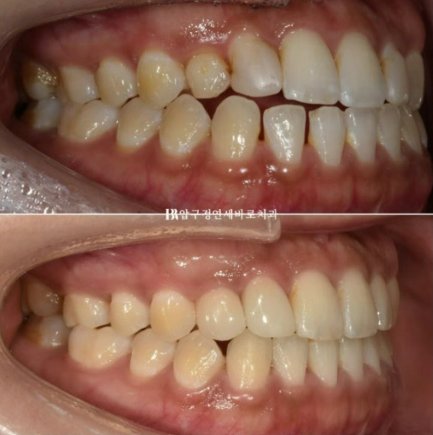

23.02~23.08